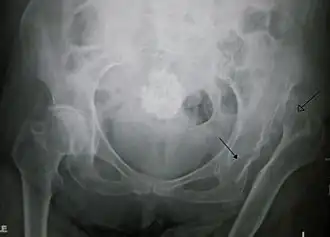

La luxation congénitale de la hanche est une affection du nouveau-né, symptomatique de dysplasie congénitale ou développementale de l'acetabulum.

Les anomalies chez le nouveau-né ou l'enfant connues sous le terme de dysplasie acétabulaire et subluxation ou luxation de la tête du fémur hors du cotyle (ou acetabulum), parce qu'ils sont présents à la naissance, sont longtemps étiquetées comme dysplasie ou luxation “congénitale” de hanche (Enseignement Hôpital Necker, Paris, Judet J. 1964)[source insuffisante].